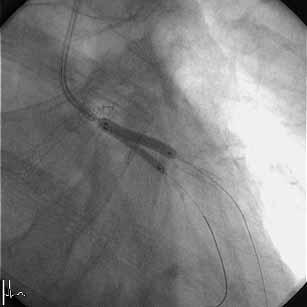

�͂��߂܂��āB���A�r58�N���̒��N��t�ł��B���͂܂��sRA�ł̃C���^�[�x���V����

�͖��o���ł��B�����~���L�b�g���łĂ���A�܂����ꂽfemoral�ł�������TFA�𑱂�

�Ă��܂������A��͂芳�҂���̖����x��radial���ォ�ȂƊ�����悤�ɂȂ�ATRA

��try���悤���Ǝv���͂��߂Ă��Ă��܂��B���낢��������Ē��������Ǝv���܂�

�̂ŁA��낵�����肢�������܂��B

�F����ɂ��ӌ��������Ǘ�̂o�b�h���s���܂����B

�VFr.TFI�A�K�C�h�J�e�W���h�L���X4.0�V���[�g�`�b�v

�P�ALAD�݂̂Ƀ��C���[�N���X���AIVUS�Ŋώ@�B

�Q�A�J���^���}�[�x���b�N4.5-8mm�ɂ�LMT�����v�����ADriver 4.0-9mm��I���B

�i�O�g���͂��Ă��Ȃ��j

�R�A�X�e���g���P�Q�C���Ŋg����AIVUS�B

�S�A�J���^���}�[�x���b�N4.5-8mm�Ō�g�����s���AIVUS�B

�T�A����ɃJ���^���}�[�x���b�N5.0-8mm�Ŋg����AIVUS���A�I���B